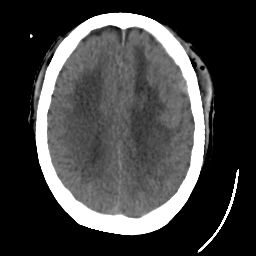

Meningioma: Roentgen-ray CT #1 -- Slice #14

[Home][Help][Clinical] Slice 14